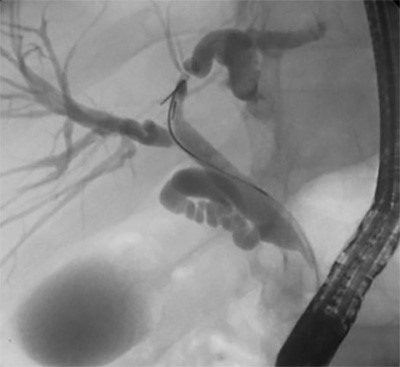

A 42-year-old Korean male presented with a one-year history of chronic, left-sided RPC resulting in a left hepatic duct stricture which only worsened the patient’s biliary disease. The patient’s treatment course included six prior ERCPs for stent placement and exchanges without improvement. At six-month follow-up, ERCP continued to show disease in the left hepatic duct (Figure 1). Unfortunately, this is a common disease trajectory for RPC and the patient was counseled to undergo hepatic resection.

Figure 1. ERCP demonstrating a persistent stricture in the left hepatic duct with post-stricture biliary ductal dilatation.